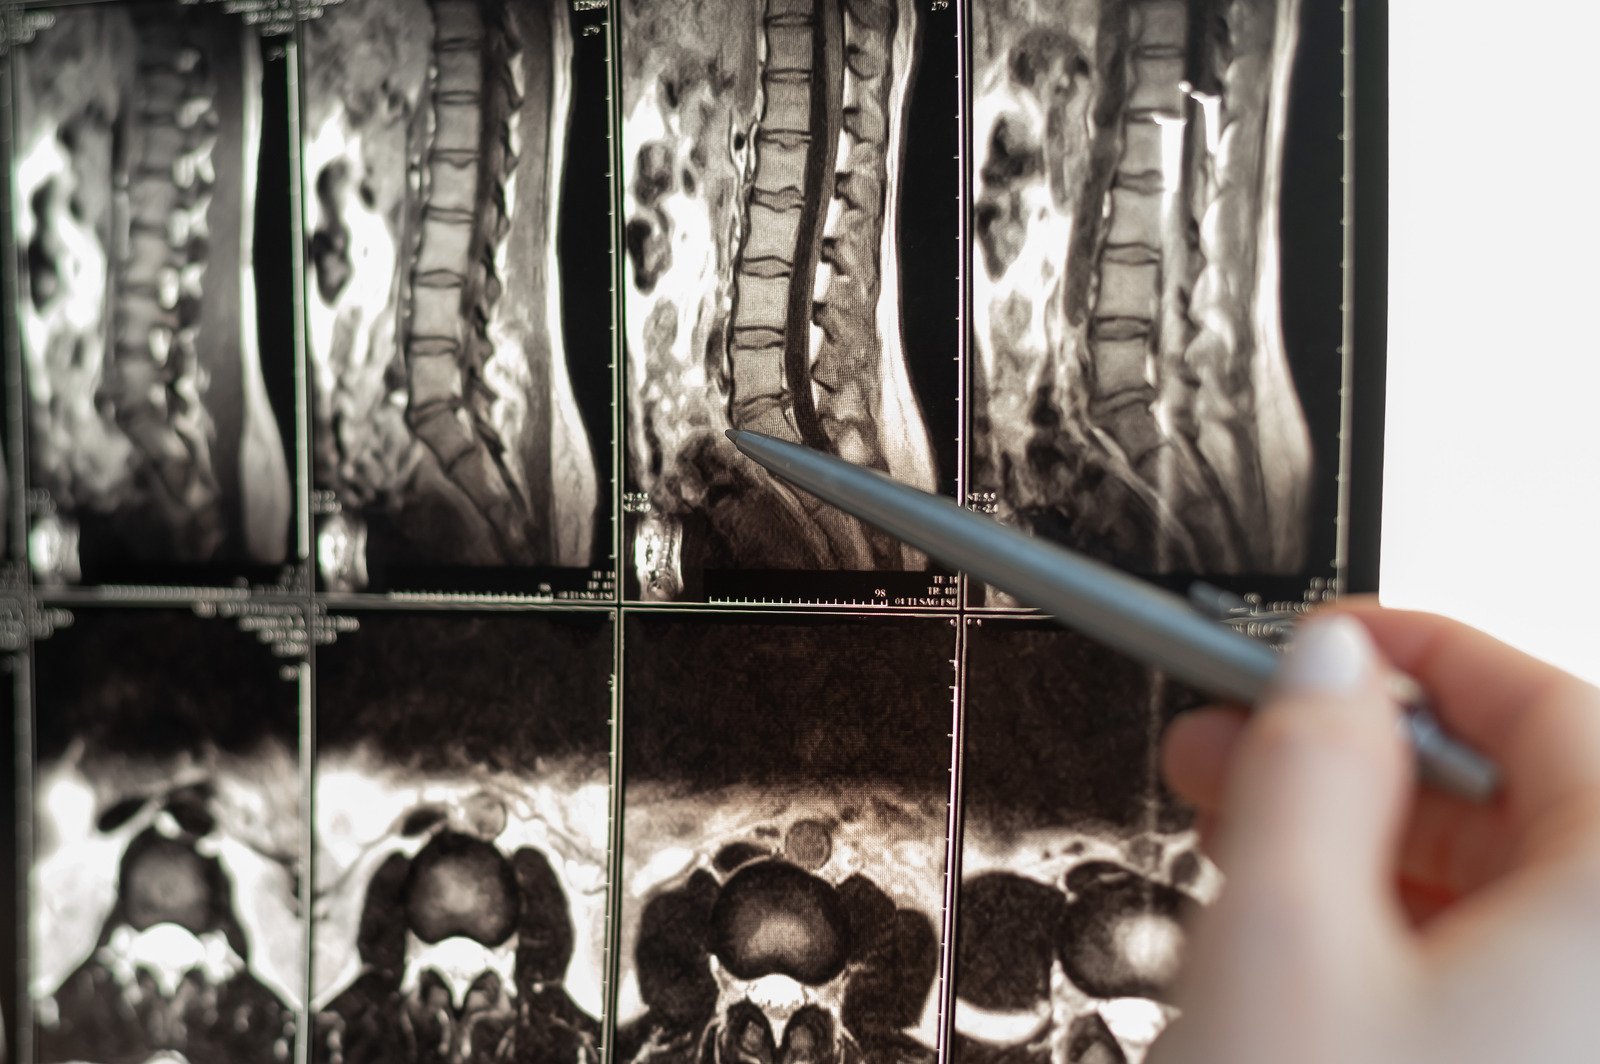

MRI: 신경 구조를 자세히 볼 수 있어 협착 부위와 정도를 정확히 파악.